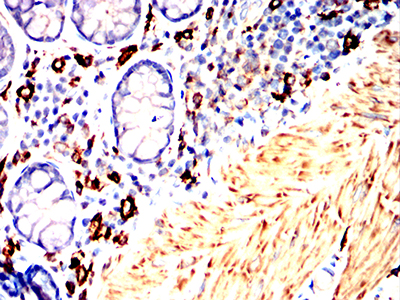

Immunohistochemical analysis of paraffin-embedded Rabbit thymus using CD163 mouse mAb with DAB staining.

-

Immunohistochemical analysis of paraffin-embedded Rabbit rectum using CD163 mouse mAb with DAB staining.

鄂公网安备42018502007531号